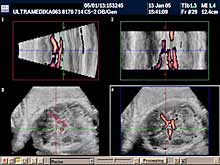

A) Savremena dijagnostika korišćenjem Broad band kolor Dopplera (Broad band-CD) i kolor Power Dopplera (CPD) bez obzira na količinu krvi koja prolazi kroz vaskularnu anomaliju i bez obzira pod kojim uglom je moguće poslati ultrazvučni talas, je u stanju da postavi dijagnozu ove ozbiljne vaskularne malformacije CNS. U nepovoljnim uslovima standardna ultrazvučna tehnika sa CD nije u stanju da prikaže ni normalne krvne sudove Wilisovog šestougla niti duboke drenažne vene . Jedino savremena ultrazvučna tehnika je u stanju da postavi dijagnozu bez obzira na položaj ploda koji obično bitno ne menja svoju poziciju u toku pregleda u III trimestru trudnoće. Takođe CPD tehnika je u stanju da proceni tačno hemodinamiku moždane i srčane cirkulacije i da tačnu prognozu. Ovo je važno jer se neke aneurizme vene Galen-i mogu lečiti nakon rađanja deteta embolizacijom krvnih sudova.

B) 3D Sono CT (trodimenzionalna) tehnika, dovodi do kvalitativnog pomaka u odnosu na prethodne godine. Naime 3D Sono CT (trodimenzionalna) tehnika nam omogućava dobijanje kompletnog volumenom mozga. Ako želimo da prikažemo u tri dimenzije krvne sudove koristimo 3D CPA tehniku. Ova tehnika je jako složena, zahteva dodatno vreme, izuzetno poznavanje anatomije i sonomorfološke ultrazvučne anatomije organa i organskih sistema, i sagledavanje promene u sve tri ravne, istovremeno. Da bi smo rendereisali - skupili sve informacije prosečno za to nam je potrebno oko 10 sekundi. Međutim, naknadnim multiplanarnim prikazivanjem i detaljnom analizom velikog broja dobijenih ultrazvučnih slika odgovarajućih preseka kompletne moždane cirkulacije potrebno nam je najmanje 10-15 minuta.

U III trimestru je moguće registrovati i druge AV malformacije mozga, koje ranije bez savremene ultrazvučne dijagnostike nisu bile moguće. Posebno treba naglasiti da jedino savremeni aparati sa Broad band CD i CPD i CPA mogu prikazati kompletnu vensku cirkulaciju sinusa neposredno ispod lobanje mozga. Takođe kodiranjem toka arterija mozga moguće je postaviti dijagnozu složene razvojne anomalije mozga (holoprozencefalije). Moramo reći da deca sa ovakvim anomalijama ne bi trebalo da budu rođena.